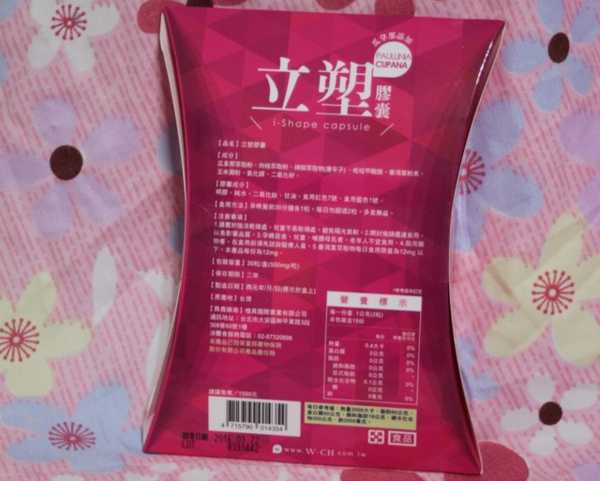

同時,謝謝【女人知己試用大隊】提供的–Supercut塑魔纖立塑膠囊

好啦,廢話不多說,就來試試繽紛小桃紅--Supercut塑魔纖立塑膠囊

每一盒Supercut塑魔纖立塑膠囊都有三小包,每一小包有10顆膠囊

Supercut塑魔纖立塑膠囊的成分有:瓜拿那萃取粉、肉桂萃取粉、辣椒萃取物(唐辛子)、吡啶甲酸鉻、番瀉葉粉末、玉米澱粉、氧化鎂、二氧化矽。

食用方式:早晚餐前30分鐘各1粒,每日不超過2粒。(多食無益)

包裝是桃紅色的